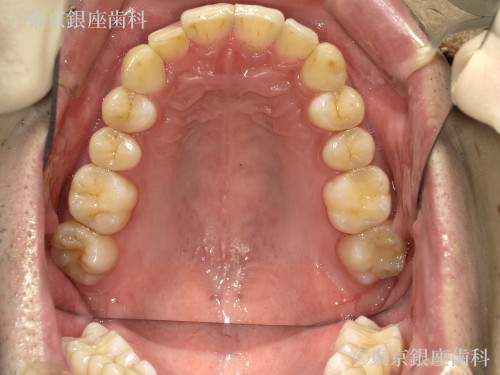

Before

側方前突